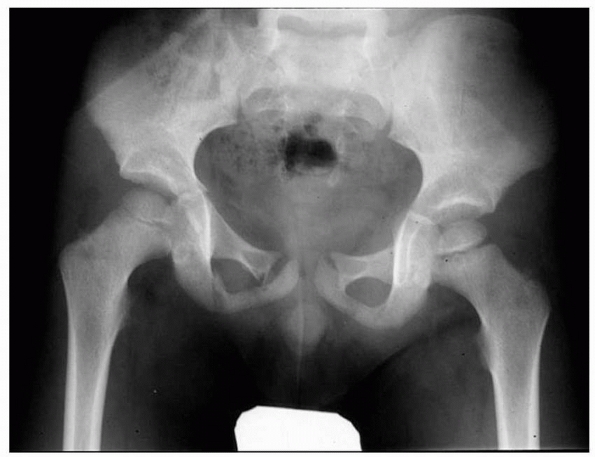

axial, CT scan are indicated to look for anterior ring fracture (Fig. 20-13).

![]() |

FIGURE 20-13 A 4-year-old with a pelvis fracture primarily with posterior involvement. A. Pelvic outlet radiograph showing a posterior injury at the sacroiliac joint. B. CT scan showing the minimal posterior SI widening. C. CT scan showing no anterior ring injury.